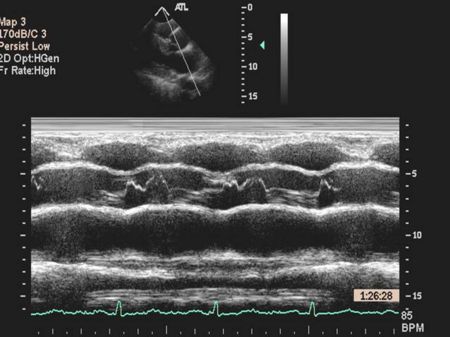

M mode echocardiography

A single crystal rapidly alternates between transmission and receiver modes with rapid updating result, rapidly moving structures (eg, valve leaflets) can be monitored for their characteristic motion very high temporal resolution

Ventricular M-mode

- Ventricular Wall Thickness

- Ventricular Chamber Size